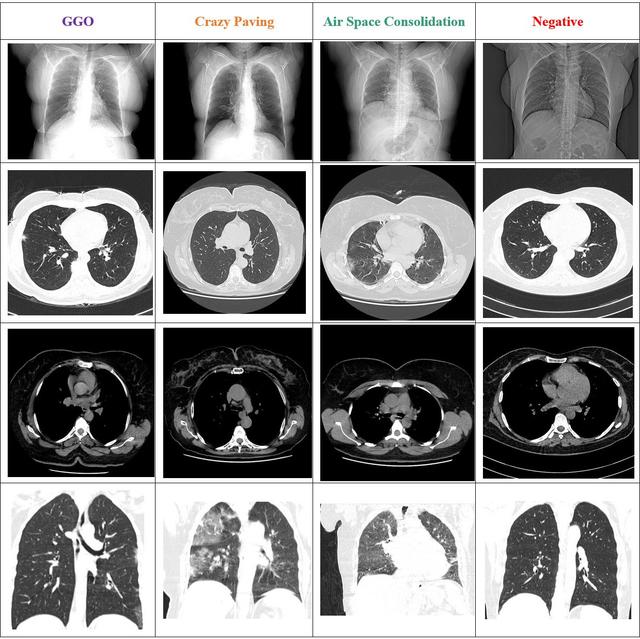

HRCTv1-COVID-19

High Resolution Chest CT-Scan Image Dataset for COVID-19 Diagnosis from 395 cases with 181,106 images. Three diagnostic labels: GGO, Crazy Paving, and Air Space Consolidation.